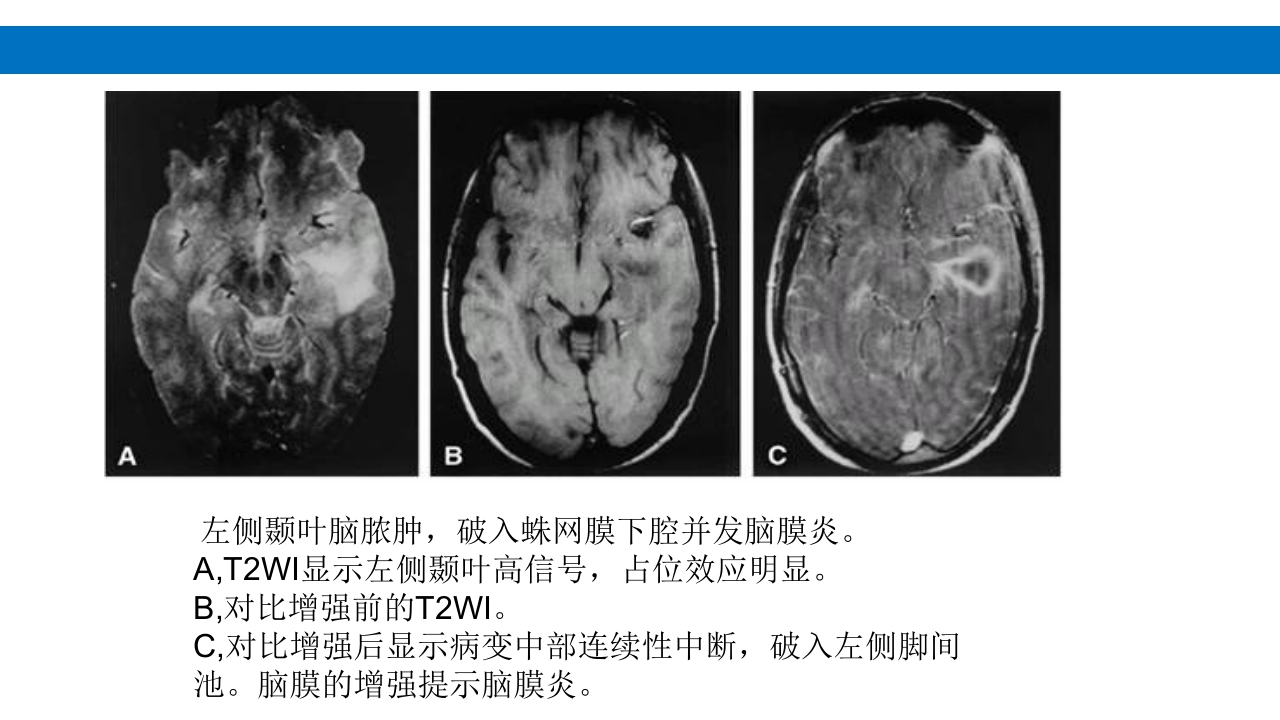

颅脑损伤的并发症及后遗症 讲解人:xxx 20XX年x月x日 1.颅骨骨髓炎 病因:为头皮软组织、中耳、乳突和副鼻窦等处炎性感染而经导 血管侵入颅骨内或颅脑开放伤感染所引起,亦可由菌血症后发生 的细菌栓子由血运转移至颅骨内。 影像学表现: 头部CT: 1.表现为不规则的蜂窝状骨质破坏区,主要位于板障,亦可累 及内外板。 2.破坏区内可见高密度的米粒状细小的高密度死骨。 3.周边可见骨质硬化增生,颅板外无骨膜反应。 4.局部的头皮可见软组织肿胀。 头部MRI: 由于受累部位细胞成分和水量增多,T1WI为低信号, T2WI为高信号,急性期边界不清,慢性期病灶局限, 边界清晰。MRI显示骨质破坏没有CT效果好。 治疗: 除应用抗菌药物控制感染外,当感染局限或已有死骨形成后, 应行手术切除感染...